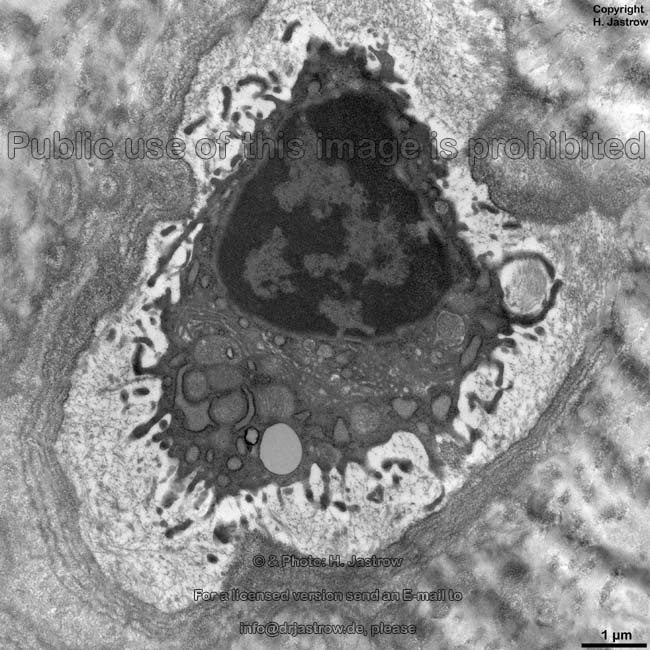

Ein bisher unbeachteter Zelltyp, Osteoblasten, -klasten und -zyten etc. Die Zellen in den Knochen welche Knochenmaterial herstellen, den Knochen auf- und abbauen.

Osteozyt:

Ähnlich wie Kollagen mit wenigen Mitochondrien ausgestattet und schwach durchblutet. Wahrscheinlich der Grund warum FC Osteorporose fördern. Gibt es Erfahrungen mit Knochenbrüchen postflox und verlängerten Heilungszeiten?